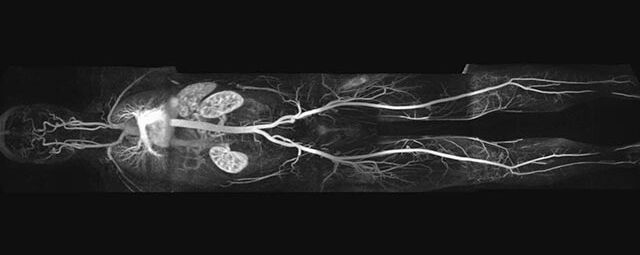

Aorta

• Bauchgefäße

• Erfassung und Verlaufskontrolle bei arteriellen Aneurysmen (Aussackungen der Arterien), vor allem der Bauchaorta

• Darstellung von Gefäßengen an Nierenarterien, Baucharterien und Becken-/Beinarterien

Ganzkörper Angiographie mit Kontrastmittel

• MR-Angiographie mit Kontrastmittel

• Erfassung arterieller und venöser Gefäße/Bypässe aller Körperregionen mit 3D-Rekonstruktion

• je nach klinischer Fragestellung zeitaufgelöste MR-Angiographie (4D-MRA) z.B. bei Frage arteriovenöse Fistel/ Shunt oder Darstellung Unterschenkelarterien vor geplanter Bypassoperation.